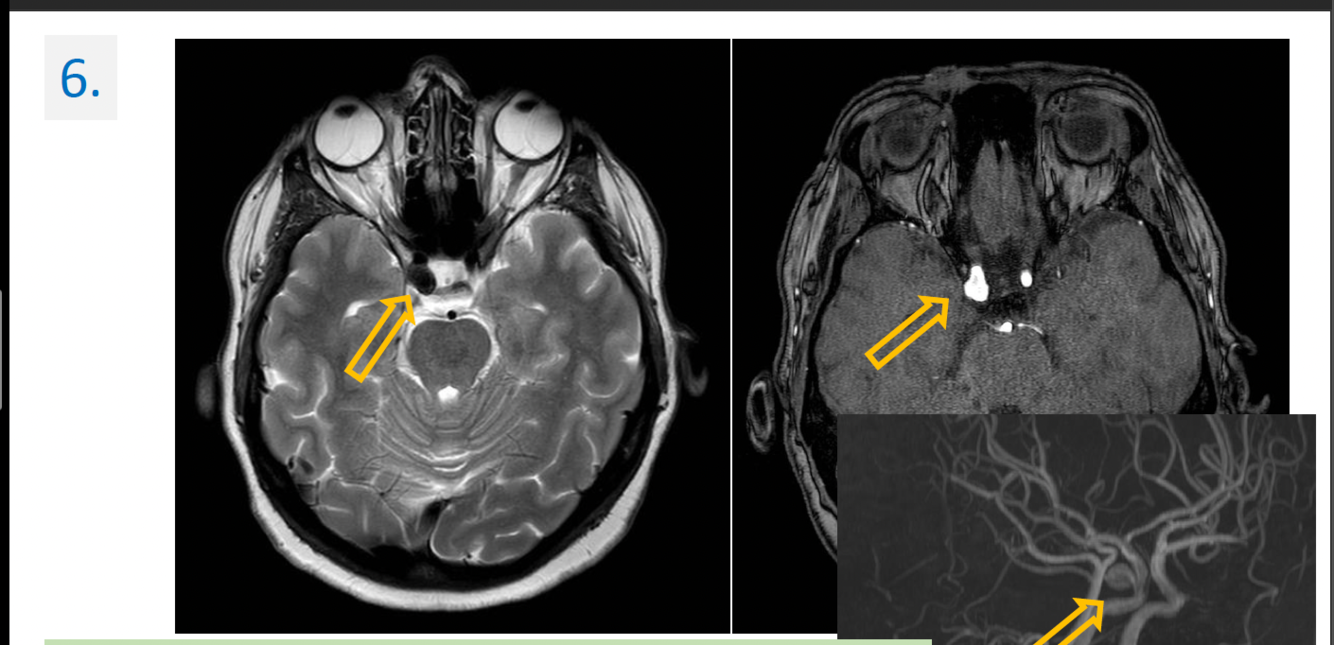

6.